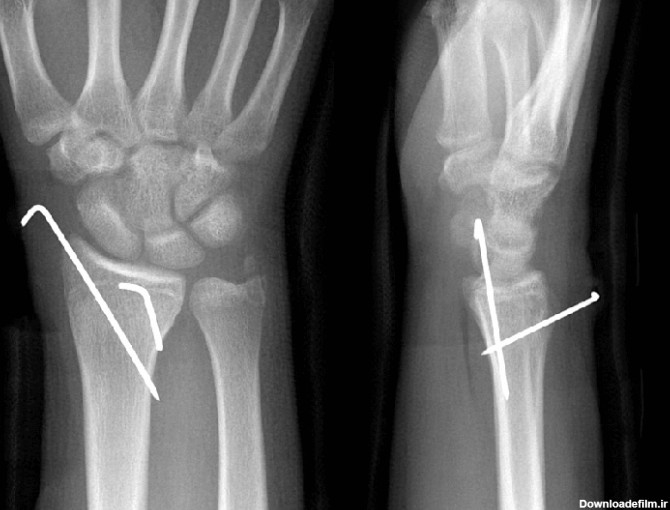

عکس پین مچ دست

تجهیزات تثبیت کننده ارتوپدی در درمان بسیاری از شکستگی ها و جراحی های ترمیمی کاربرد وسیعی دارند. بسیاری از موارد شکستگی های همراه با جابجایی استخوان با عمل جراحی درمان می شوند و در اغلب آنها از تجهیزات تثبیت کننده (ایمپلنت) داخلی، خارجی و یا داخل کانال استخوانی به منظور ثابت کردن و تنظیم جایگاه …